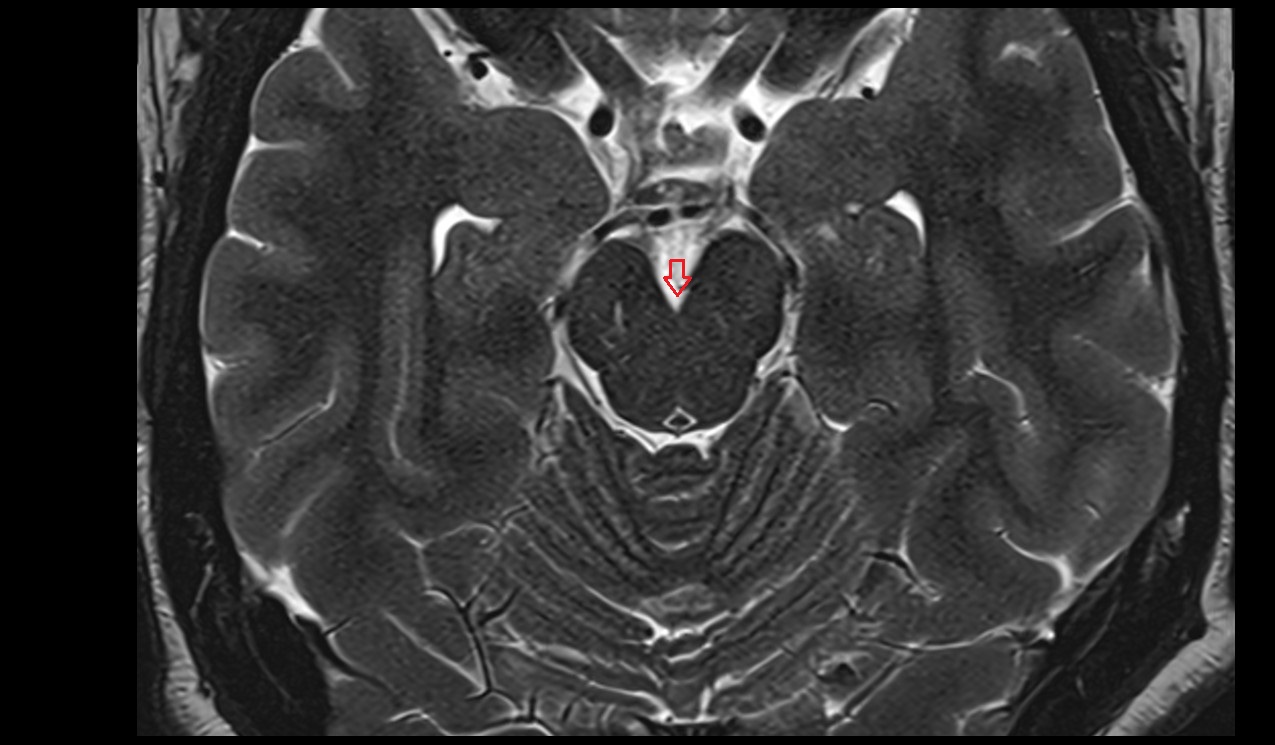

- Peripheral zone of prostate

- Anterior Fibromuscular Stroma of prostate

- Central zone of prostate

- Transitional zone of prostate